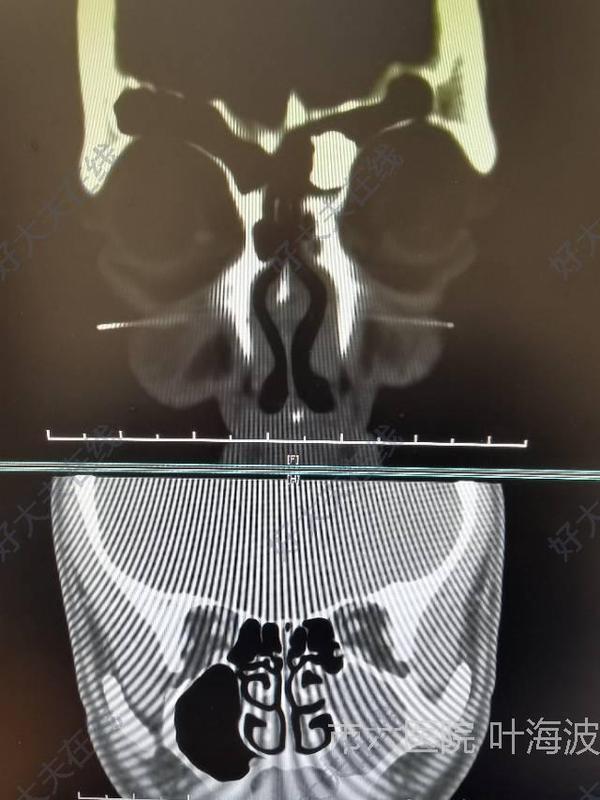

鼻竇骨瘤手術(shù)

葉海波醫(yī)生的科普號2021年04月18日356